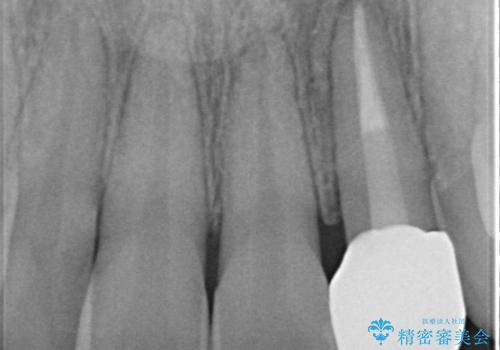

- 前歯の変色を主訴に来院されました。

根管治療後、オールセラミッククラウン(エクセレント)にて治療を行なっています。